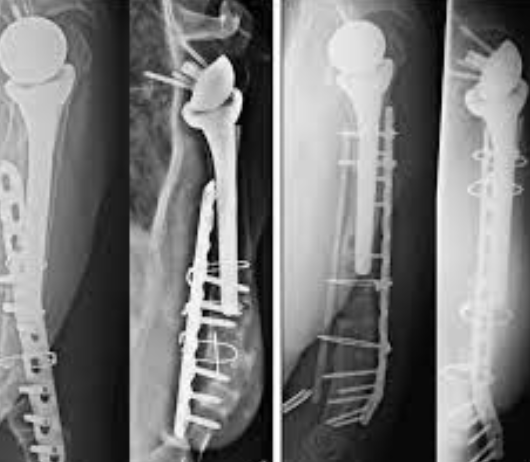

Addressing Non-Unions and Revision Trauma with Dr....